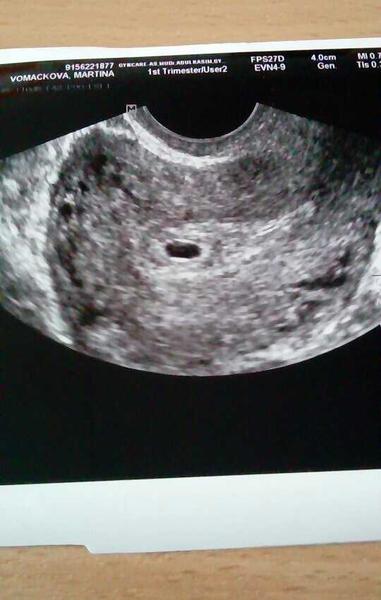

Prave jsem se vratila z nemocnice s krvacenim 😢 mam tam totiz mensi hematom. Na utz vacek se zloutkovym 5+3tt.... a druhy vacek 4+6 😁😂

@crazynaa gratulace 😉 to je krásný. My dneska byli potvrdit a jsme šestý týden

@crazynaa zatím nebylo vidět ☹ říkal ale že máme přijít za týden že by vidět být už snad mělo. U malé jsem srdíčko měla až v osmém týdnu tak zatím hlavu nevesim

@martina16horysek jooo to je ještě brzy, mě říkal dr že srdíčko většinou naskočí tak 6+3,já byla 6+1 a ještě nebylo... takže rozhodně je čas 😉